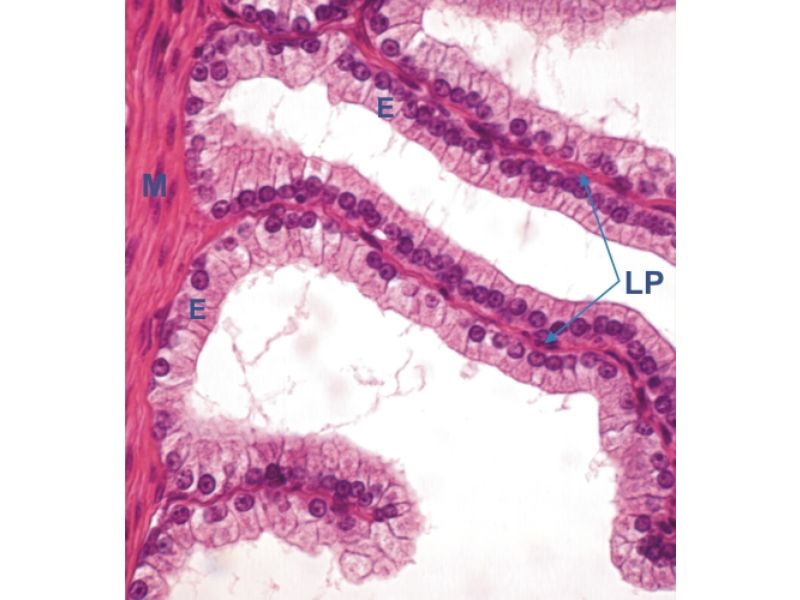

Vesicula seminalis

Slide 81Vesicula seminalis

- Mucosa

- Epithelium

- Lamina propria

- Muscle layer

Mucosa

- Lumen

- Irregular

- Store secretions

- Pseudostratified columnar epithelium

- Lamina propria

- Contains AVL

- Folded mucosa ^^ surface area

Muscle layer

- Inner circular

- Outer longitudinal